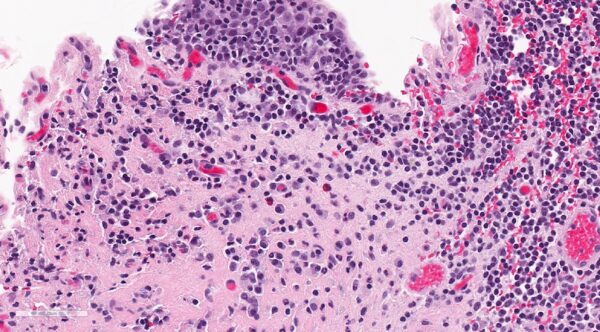

La cistoscopia es otra herramienta diagnóstica que puede ser utilizada para examinar directamente el interior de la vejiga y observar signos característicos de la cistitis intersticial. Durante este procedimiento, pueden observarse glomerulaciones, que son hemorragias submucosas en la mucosa vesical. Estas glomerulaciones se pueden visualizar especialmente cuando se realiza una distensión hidrostática de la vejiga, un procedimiento en el que se introduce agua en la vejiga para expandirla y facilitar la visualización de la mucosa. Si bien las glomerulaciones son indicativas de cistitis intersticial, no son siempre presentes en todos los casos, y su ausencia no descarta el diagnóstico.

Si se observan lesiones sospechosas durante la cistoscopia, como áreas de sangrado o tumores, se debe realizar una biopsia para excluir otras posibles causas de los síntomas, como carcinoma de vejiga, cistitis eosinofílica o cistitis tuberculosa. Estas condiciones pueden presentar signos clínicos similares a los de la cistitis intersticial, pero requieren tratamiento específico y tienen implicaciones pronósticas diferentes.

En cuanto a la presencia de células mastocíticas submucosas, aunque se ha observado que los mastocitos pueden estar involucrados en la inflamación crónica de la vejiga, su presencia no es un requisito diagnóstico para la cistitis intersticial. El diagnóstico se basa en la exclusión de otras causas y en la identificación de los síntomas característicos, como el dolor al llenar la vejiga y la mejoría al vaciarla.